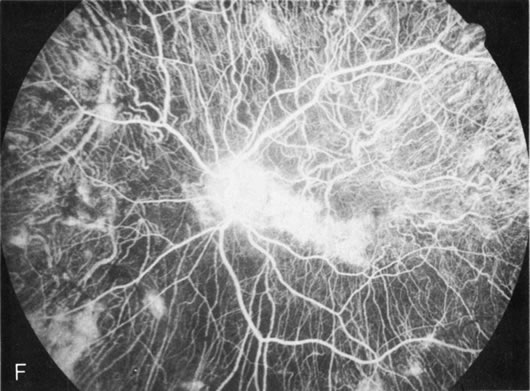

Fig. 6. Generalized choroidal dystrophy. This 65-year-old woman gradually developed enlarging, progressive areas of choroidal atrophy over a 20-year period. When initially seen, the abnormalities were confined to the peripapillary and macular region (A,B). In a recent examination, the generalized choroidal atrophy is vividly demonstrated on angiography (C–F).

Generalized choroidal dystrophy is usually noted in middle-aged mildly symptomatic individuals who show a predominantly peripapillary or pericentral distribution of choroidal atrophy. Gradually, over the years these areas enlarge to eventually involve the entire retina. These changes are vividly seen on FA (Fig. 6).